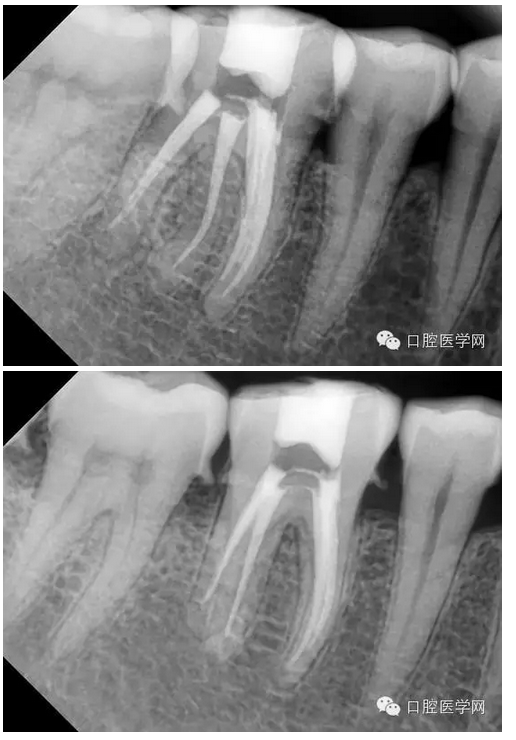

下六五根管治療一例

患者:男,44歲

主訴:右下后牙進(jìn)食痛2周,加重2天。

現(xiàn)病史:牙齒有洞,無不適,未處理,2周前開始進(jìn)食痛,口服消炎藥,好轉(zhuǎn),2天前晚上劇烈疼痛,今來看診。

檢查:#46牙頰側(cè)小洞,探(++),叩(-),冷熱(+++),咬頜正常,牙齦未見不適,未見其它不適。

診斷:#46牙髓炎

治療計(jì)劃:#46根管治療+冠修復(fù)保護(hù)。